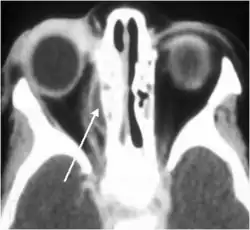

Воспаление околоносовых пазух, прежде всего клеток решётчатого лабиринта (этмоидит), в ряде случаев вовлекает в воспалительный процесс периорбиту (периостит). В некоторых случаях гнойный экссудат отслаивает периорбиту от медиальной стенки глаза с формированием субпериостального абсцесса.